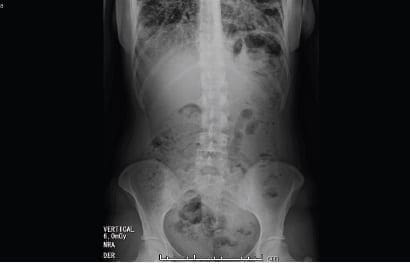

Y se decidió tomar tomografía computarizada de tórax de alta resolución (TCAR) (figura 1), cuyos hallazgos anormales se reportaron como consolidaciones bibasales confluentes y en lóbulo medio por probable neumonía multilobar y consolidaciones en lóbulos superiores; no se identificaron masas pulmonares ni derrame pleural, lo cual era concordante con la impresión diagnóstica inicial de neumonía.

Figura 1. Tomografía de tórax de alta resolución

con imagen de consolidaciones bibasales confluentes.